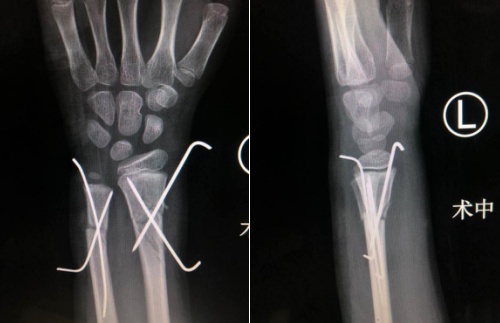

熊祖国手术团队经讨论男孩的手术方案为闭合复位尺桡骨远端骨折,钢针内固定。尽管“闭合复位”对手术医师的技术、检查及手术配合设备等方面有更高的要求,但对患者治疗和恢复都更好一些。这种治疗方法优点是创伤小、无手术疤痕、住院时间大大缩短、孩子恢复快,并发症少,针尾可露于皮外,术后复查骨折愈合良好即可门诊取出钢针、无需再次住院手术。

明确手术方案后,熊祖国医师为男孩安排了手术,术中在助手牵拉对抗下牵引予以复位左尺桡骨骨折端,各以两根金属骨针交叉打入内固定,术中一切顺利,术后复查x线片,见各骨折复位良好,内固定在位。